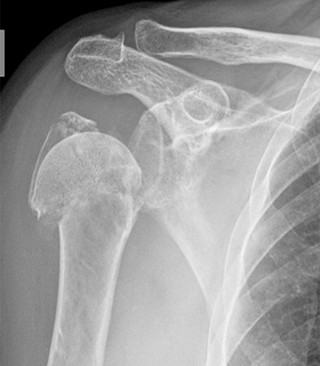

Η αρθρίτιδα του ώμου μπορεί να οφείλεται σε χρόνιες βλάβες των τενόντων του ώμου (ονομάζεται στροφικό πέταλο και είναι κυρίως ο υπερακάνθιος τένοντας) ή σε παλιές κακώσεις και κατάγματα που έμειναν χωρίς καλή αντιμετώπιση.

Στην αρθρίτιδα καταστρέφεται ο χόνδρος της άρθρωσης, έρχεται σε επαφή κόκκαλο με κόκκαλο και εκτός του πόνου χάνεται και η κινητικότητα της άρθρωσης του ώμου. Ο ασθενής δυσχεραίνεται στην καθημερινότητά του.

Δυσκολεύεται να ντυθεί, να ξυριστεί, χτενιστεί. Η διάγνωση τίθεται με την εξέταση (δεν γίνονται οι φυσιολογικές κινήσεις, άνοιγμα και στροφές) και επιβεβαιώνεται με την ακτινογραφία (όχι μαγνητική) που δείχνει και το βαθμό της βλάβης.

Η αρθρίτιδα του ώμου αντιμετωπίζεται μόνο χειρουργικά εφόσον προκαλεί πόνο και δυσχεραίνει την καθημερινότητα του ατόμου. Η ενδεδειγμένη εγχείρηση είναι η ολική αρθροπλαστική που ονομάζεται «ανάστροφη» λόγω της κατασκευής της. Αποδίδει ένα χέρι πολύ πιο λειτουργικό από πριν και ανώδυνο στην κίνηση.